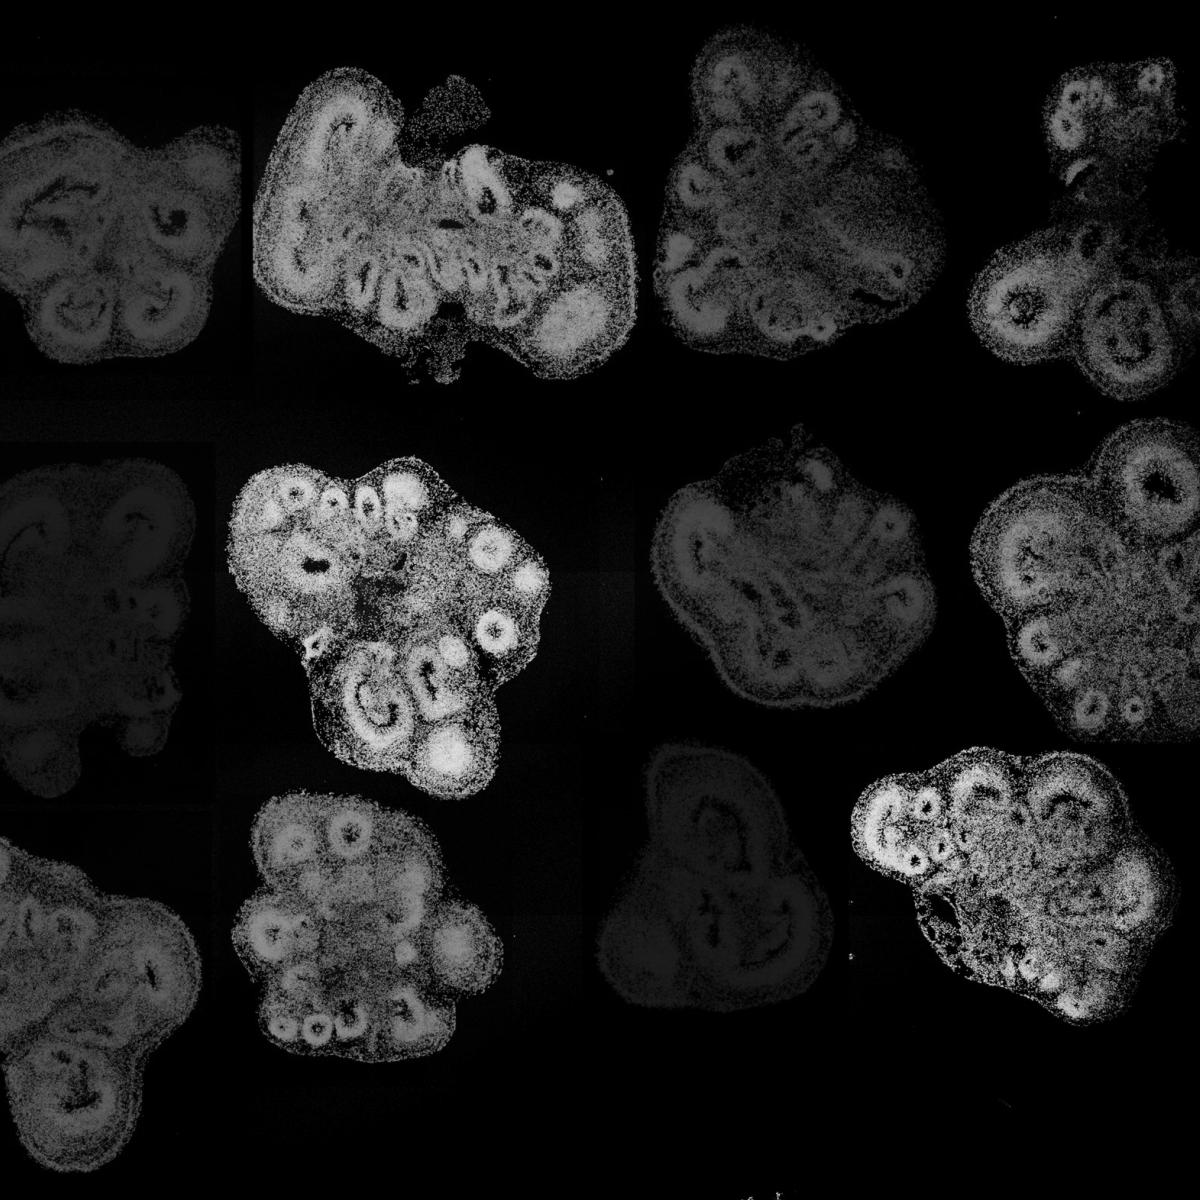

Most recently, he has been leveraging his understanding of these developmental processes to create simplified models of brain and spinal cord tissues from human embryonic and induced pluripotent stem cells using 3D organoid approaches. These technologies offer an unprecedented opportunity to investigate features of human development and pathologies that cannot be easily recapitulated in model organisms such as mice.

Utilizing these 3D brain organoids, Novitch models the formation and function of human neural circuits to better understand the basis of neurodevelopmental and neuropsychiatric disorders, as well as the root causes of neurodegenerative diseases such as spinal muscular atrophy and amyotrophic lateral sclerosis. He seeks to use this experimental platform for drug discovery and the development of cellular therapies to repair the injured or diseased nervous system.